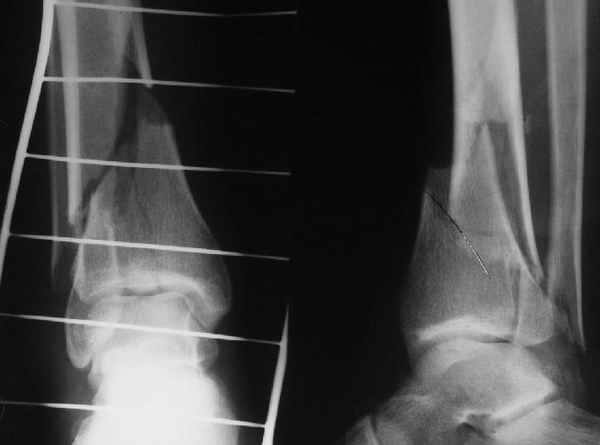

Pilon fracture:

ET> ЕЧ При подобных переломах фиксация малоберцовой кости обеспечивает

ET> низведение латерального тибиального фрагмента - появляется ориентир для

-Появляется ориентир и остов, на чем можно строить восстановление, почему сперва малоберцовую, впервые обьяснили и описали (Pylon type and Ankle fractures) в середине 50х Rienau и Gay.

Восстановливая длину и ротацию малоберцовой кости, затем относительно легче произвести реставрацию остальных элементов перелома дистального эпиметафиза болшеберцовой кости.

конец малоберцевой кости, к нему прикрепляется латеральный суставной фрагмент дистального эпиметафиза большеберцовой кости (как на снимке)

и таранная кость, которые при репозиции малоберцовой кости репонируются автоматически.

Дистракция в аппарате или на вытяжение результат - лигаментотаксис, посмотреть бы, как сегодня расположены отломки.